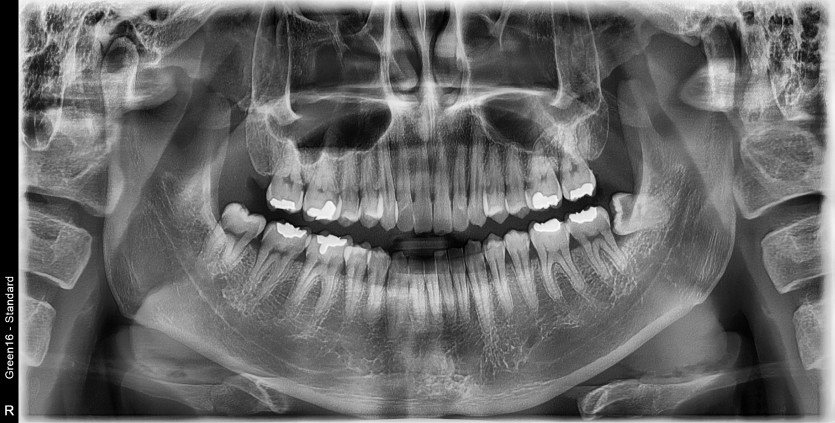

#38, 48 사랑니 발치

구강외과 전문의가 당일발치했습니다.